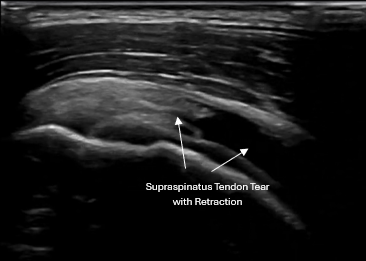

Dynamic shoulder ultrasound exam showing acute bursitis with rotator cuff tear in active adult

Using real-time musculoskeletal ultrasound, we evaluate for:

Rotator cuff pathology

• Supraspinatus tendinopathy or tears

• Infraspinatus involvement

• Subscapularis pathology

• Partial-thickness and select full-thickness tears

Ultrasound allows us to see the injury directly, assess it dynamically, and compare to the opposite side when needed

Musculoskeletal ultrasound image showing rotator cuff tendon injury